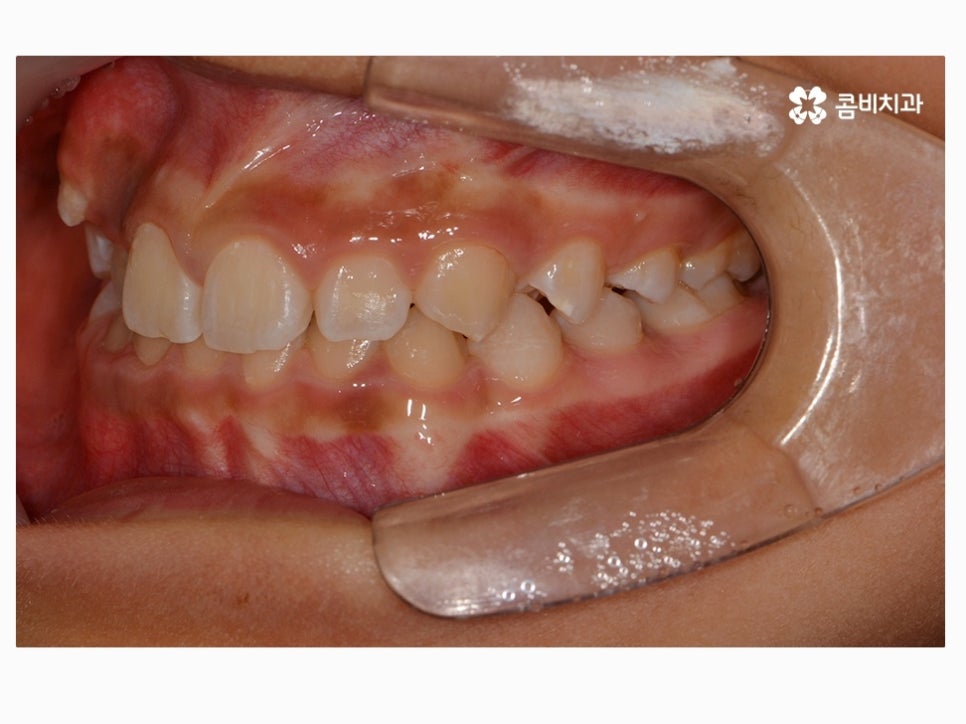

부정교합을 치료하는 방법은 나이대와 어떤 상태인지 진단에

따라서 달라질 수 있는데 위 케이스처럼 일반적인 치아교정으로

진행이 되는 경우도 있고 구외 교정 장치를 활용하는 경우 등 진단에 따라 다양할 수 있어요.

위 환자분께서 사용하신 장치는 클리피씨로 자가 결찰 장치이며

초기 통증이 줄어들고 관리가 용이하며 시술 기간을 단축시킬 수 있다는 장점이 있어요.